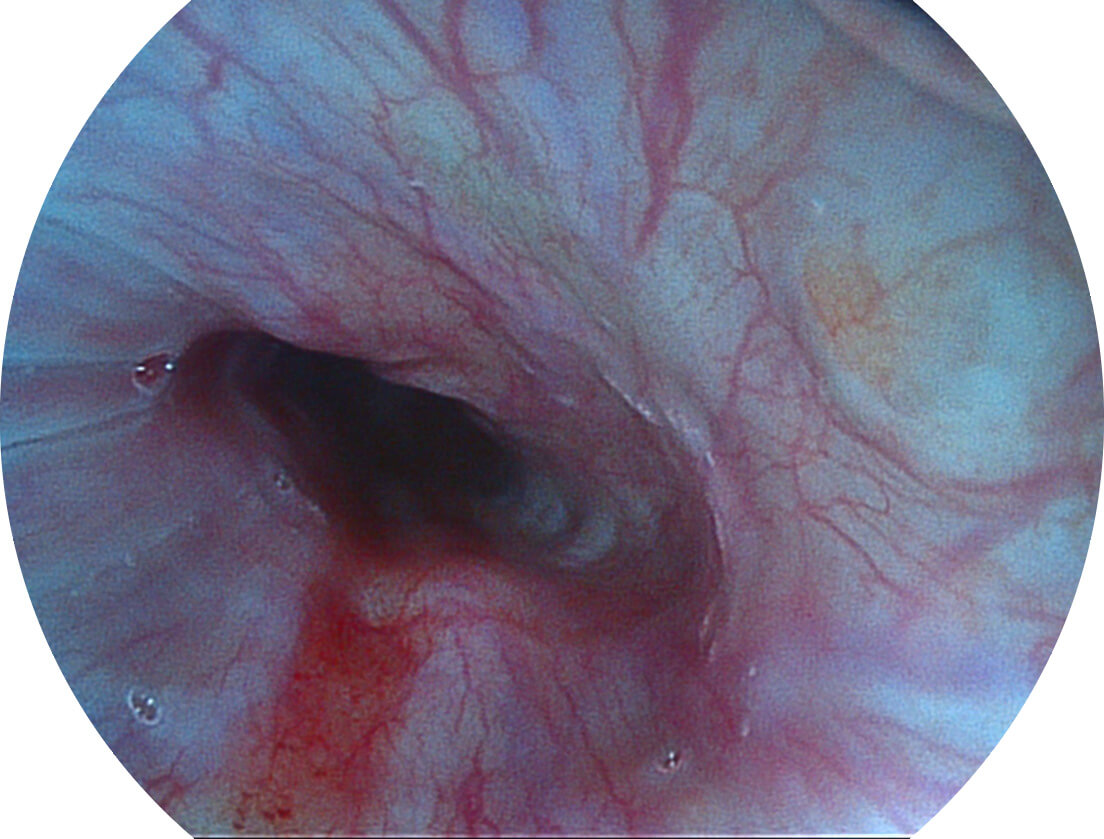

白光图像

SFI图像